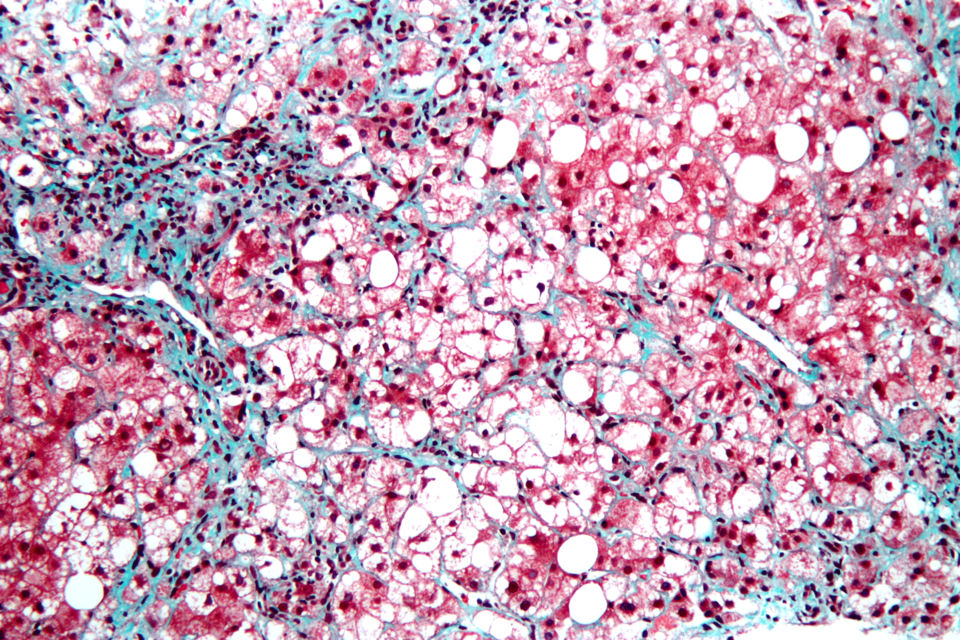

Bei der nicht-alkoholischen Steatohepatitis ist es wichtig, das eigene Körpergewicht zu reduzieren. Bei der nicht-alkoholischen Steatohepatitis ist es wichtig, das eigene Körpergewicht zu reduzieren. © wikimedia/Nephron (CC 3.0)

Hochvergrößerte mikroskopische Aufnahme einer Steatohepatitis Hochvergrößerte mikroskopische Aufnahme einer Steatohepatitis © wikimedia/Nephron (CC 3.0)